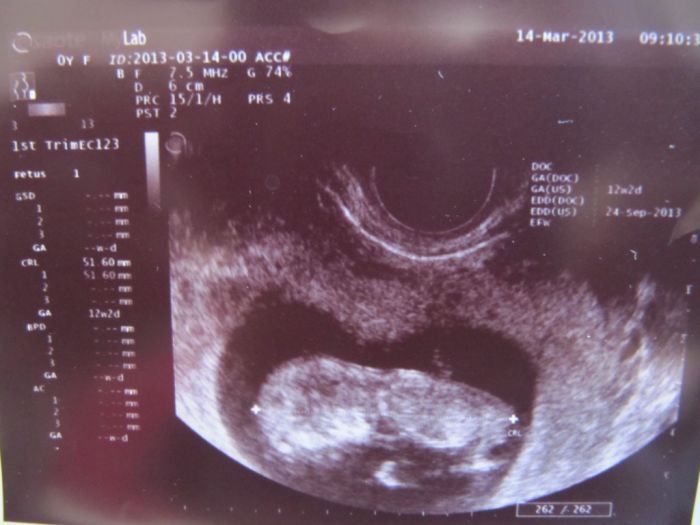

a už jsme viděla jak se krásně vrtí:) a taky jsme dostali těhu průkaz hurá!! Na ten screning jsem objednaná na 5.4. ale ještě nevím jestli tam půjdu ... No uvidím. Přikládám fotečku

A máš tu krásnou fotečku drobka

Zkusím ji sem taky vložit

Marse, ty jo, to je už úplné miminko